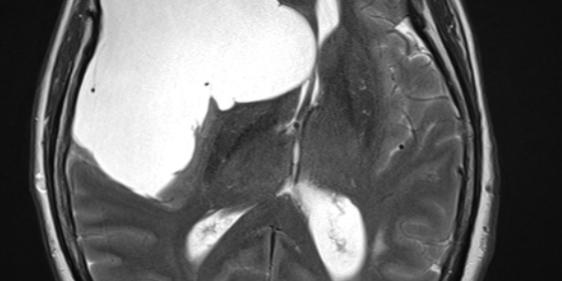

Η μαγνητική εγκεφάλου ανέδειξε ευμεγέθη αραχνοειδή κύστη δεξιά κροταφικά με σημαντική πίεση επί του υγιούς εγκεφάλου και παρεκτόπιση των δομών της μέσης γραμμής (έμμεση ένδειξη αυξημένης ενδοκράνιας πίεσης).

Στη συγκεκριμένη περίπτωση όμως η κύστη ήταν εξαιρετικά μεγάλη και πίεζε σημαντικά τον παρακείμενο εγκέφαλο. Αυτό φαίνεται ξεκάθαρα από τη λεγόμενη “παρεκτόπιση των δομών της μέσης γραμμής”. Αυτό σημαίνει ότι ο εγκέφαλος πιέζεται από τη μία μεριά τόσο πολύ, που οι φυσιολογικές εγκεφαλικές δομές παρεκτοπίζονται. Επιπλέον, η αυξημένη ενδοκράνιος πίεση προκάλεσε οίδημα στα οπτικά νεύρα, γι’ αυτό και η ασθενής είχε προβλήματα με την όρασή της.